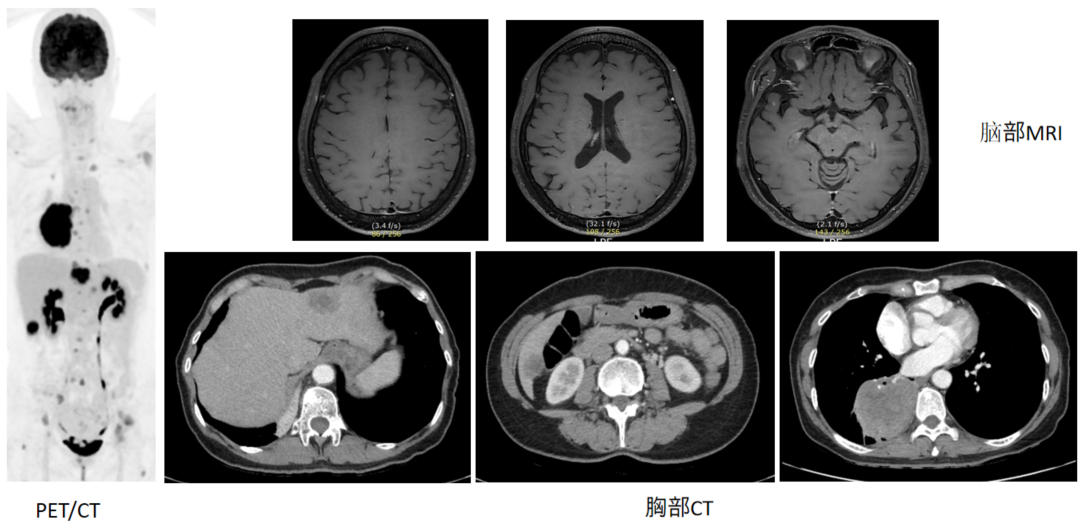

影像学检查(2025年7月1日):CT及PET-CT显示右下叶巨大肺肿块,伴多发骨、肝转移。MRI显示多发脑病灶。

临床诊断:肺腺癌,IV期,EGFR Ex19Del,MET过表达,多发 骨转移、肝转移、脑转移。

疗效评估: 仅治疗1个月后,右下叶巨大原发灶及肝脏转移灶体积缩小超过80%,达到深度缓解。2025年11月1日及11月3日的影像学复查证实,患者持续维持深度缓解状态。

颅内病灶在MRI上几乎完全消失或仅残留针尖样微小病灶。

病例二具有典型的“难治”特征:EGFR突变合并MET过表达、脑转移、肝转移及ctDNA阳性。MARIPOSA研究的亚组分析已提示,包括脑转移、肝转移及TP53共突变等患者在内的预设亚组埃万妥单抗联合兰泽替尼均显示出一致的获益趋势[6]。该病例在治疗首月即实现颅内外的全面深度缓解,肺部病灶及肝脏转移灶体积缩小超过80%,颅内病灶几乎完全消失,这也成功印证了这一联合治疗方案在EGFR突变NSCLC高危亚组中的卓越疗效。